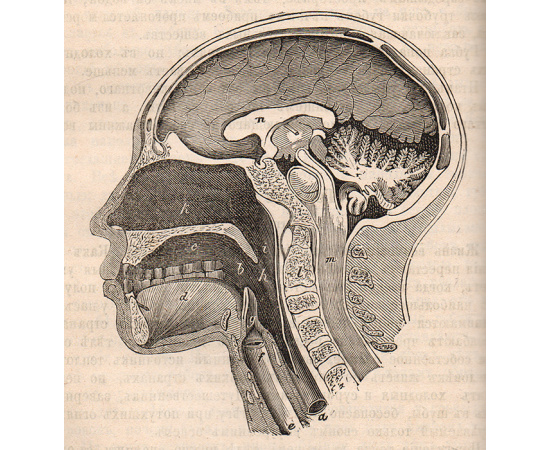

В книге также присутствуют иллюстрации и фотографии, которые визуально дополняют тексты и помогают детям лучше визуализировать представленные материалы. Это помогает им увидеть реальные образцы и примеры из окружающего мира и более полно воспринять их.

В книге также присутствуют иллюстрации и фотографии, которые визуально дополняют тексты и помогают детям лучше визуализировать представленные материалы. Это помогает им увидеть реальные образцы и примеры из окружающего мира и более полно воспринять их.